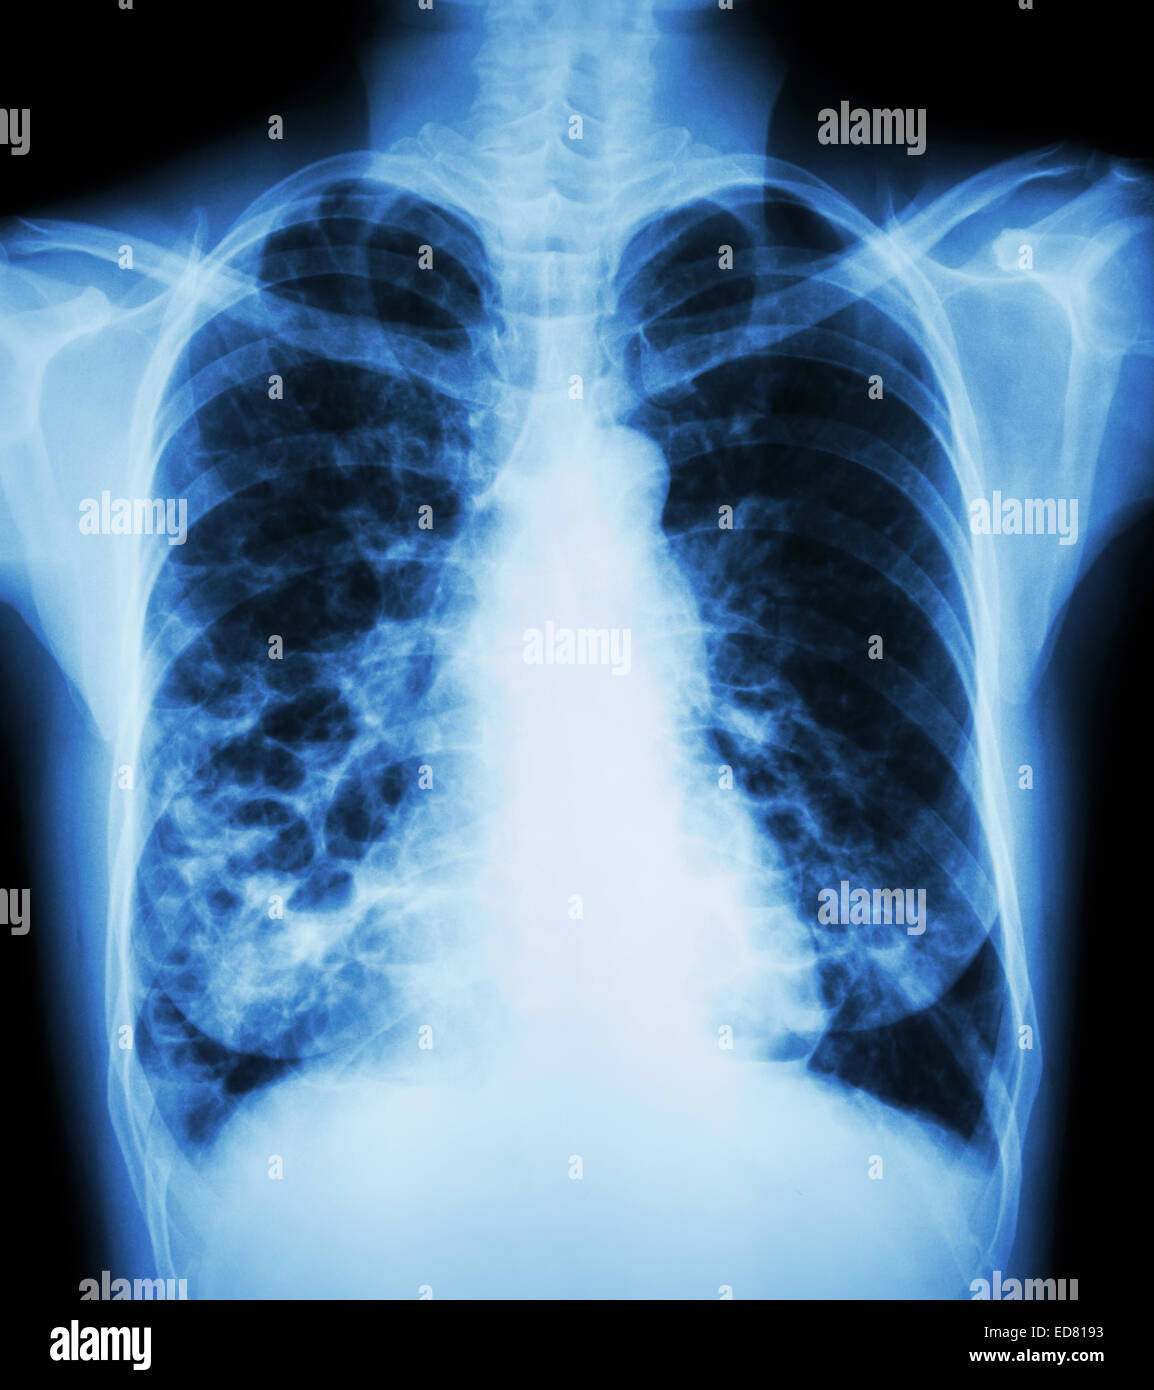

From www.alamy.com

"Bronchiectasis" Xray chest show multiple lung bleb and cyst due to Can Bronchiectasis Be Seen On Xray When asking a radiologist about the definition of bronchiectasis, the answer will. A provider uses a machine to take pictures of your lungs to see if your airways are damaged. Bronchiectasis is dilation and destruction of larger bronchi caused by chronic infection and inflammation. Bronchiectasis and small airways disease. Chest ct scan if indicated (e.g., hemoptysis, or concern for pulmonary.. Can Bronchiectasis Be Seen On Xray.